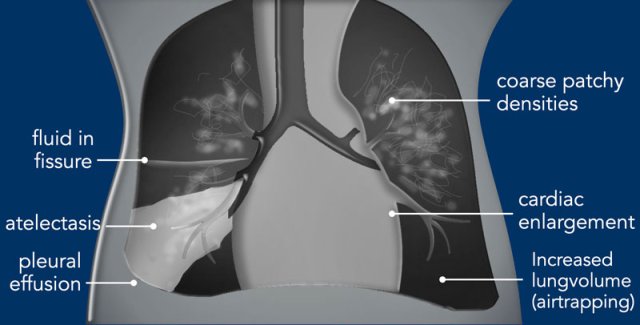

Imaging

• Mild increased lung volume.

• Interstitial edema resulting in perihilar linear densities.

• Subtle enlargement of the cardiac silhouette.

• Pleural effusions and fluid in the fissures.

• The radiological findings may be asymmetrical.

• Increased lung volume due to air trapping.

• Bronchiolitis can lead to atelectasis and air trapping.

• Complete obstruction of the bronchus can lead to atelectasis.

• Coarse, diffuse bilateral patchy or more linear opacification.

• Can present asymmetrical.

• Pleural effusions can be seen.

• In a later stage persistent pulmonary hypertension present as cardiomegaly on the x-ray.